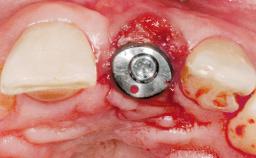

Immediate Placement of an Implant in a Maxillary Left Central Incisor Site

A 33-year-old female patient presented with an upper left central incisor that required extraction after a failed endodontic therapy. The tooth had been traumatized when the patient was a teenager and had undergone several endodontic treatments, including two apicectomy procedures. The patient was in good health and did not smoke. Clinical examination showed that the patient had a high lip line. In full smile, the gingival margins of the upper teeth were visible to the first molars. The gingival margins of central incisors 11 and 21 were only just showing. Examination of tooth 21 confirmed that the tooth was mobile and had hypererupted by 1 mm.

Type of Implants One-Piece

Bone Augmentation Horizontal|Simultaneous

Augmentation Materials Xenogenous|Membrane

Placement Protocol Immediate implant placement

Tooth Site Maxillary incisor or canine

Socket Morphology Single-root socket

Socket Integrity Damage to one or more bone walls

Bone Volume Damage to one or more socket walls